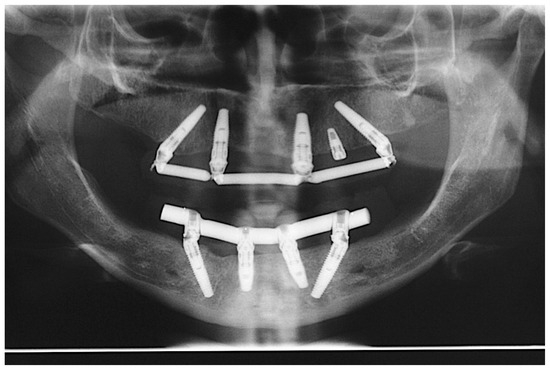

The patients were offered all possible treatment options, so they could choose which treatment plan was more adequate for each patient. Those enrolled in the study chose the procedure and authorized it by signing a term of consent in accordance with the Helsinki Declaration (1975, revised in 2013). The primary goal was to achieve sufficient initial stability to perform immediate loading, and thus, in some cases, sub-instrumentation of the implant sites could be performed in order to ensure this objective. The choice for sub-instrumentation was left for the surgeon to decide, regardless of the region, whenever they felt the bone density appeared to be D3 or D4 [18], according to their experience. In regions with a denser bone or cortical (D1 or D2), conventional instrumentation was performed. At least 45 Ncm of initial torque was necessary to continue with the immediate loading, but higher values could be reached if possible [12]. Diagnosis and treatment planning included study models articulated in a semi-adjustable articulator, clinical photographs, panoramic radiographs (Figure 1) and cone-beam computed tomography (CBCT) imaging exams to identify the anatomical structures and visualize the presence of any pathology. After the oral rehabilitation project was ready, a multifunctional guide to determine the best implant placement positions was fabricated.

Figure 1.

Baseline panoramic radiograph.

Patients were followed up for two years after implant installation, according to the following appointment schedules: time intervals of 7 days, 60 days, 6 months, 12 months, 18 months and 24 months [21]. The success criteria used in this study were, as suggested by Misch [23], no mobility, no pain during function, less than 2 mm of radiographic bone loss after initial surgery and no history of exudates. The clinical parameters of the implants were assessed during all follow-up appointments. Patients were examined using periodontal probing, CT scans, radiographs (Figure 13), intra- and extra-oral photographs and ISQ assessment.

Figure 13.

Two-year follow-up control panoramic radiograph.